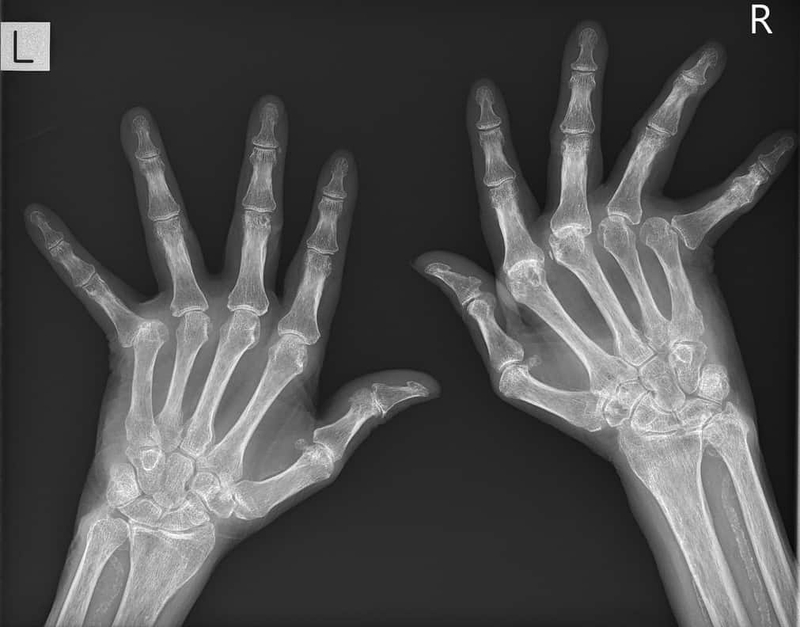

• Chẩn đoán hình ảnh: X-quang (hình ảnh mất chất khoáng đầu xương, bào mòn xương, hẹp khe khớp), chụp cộng hưởng từ, siêu âm khớp.

• X - quang điển hình ở khối xương cổ tay.

Biến dạng khớp bàn ngón tay, ngón chân

Một trong số các biến chứng phổ biến và dễ gặp của viêm khớp dạng thấp đó là biến dạng các khớp ở bàn ngón tay, bàn ngón chân.

Bàn tay gió thổi (lệch trụ), cổ tay hình lưng lạc đà, ngón tay hình cổ cò, ngón tay của thợ thùa khuyết, ngón gần hình thoi, các khớp bàn ngón biến dạng, gan bàn chân tròn, ngón chân hình vuốt thú,... là những biến dạng thường thấy ở những người bệnh có nhiều đợt tiến triển bệnh hoặc sau một thời gian diễn biến mạn tính.